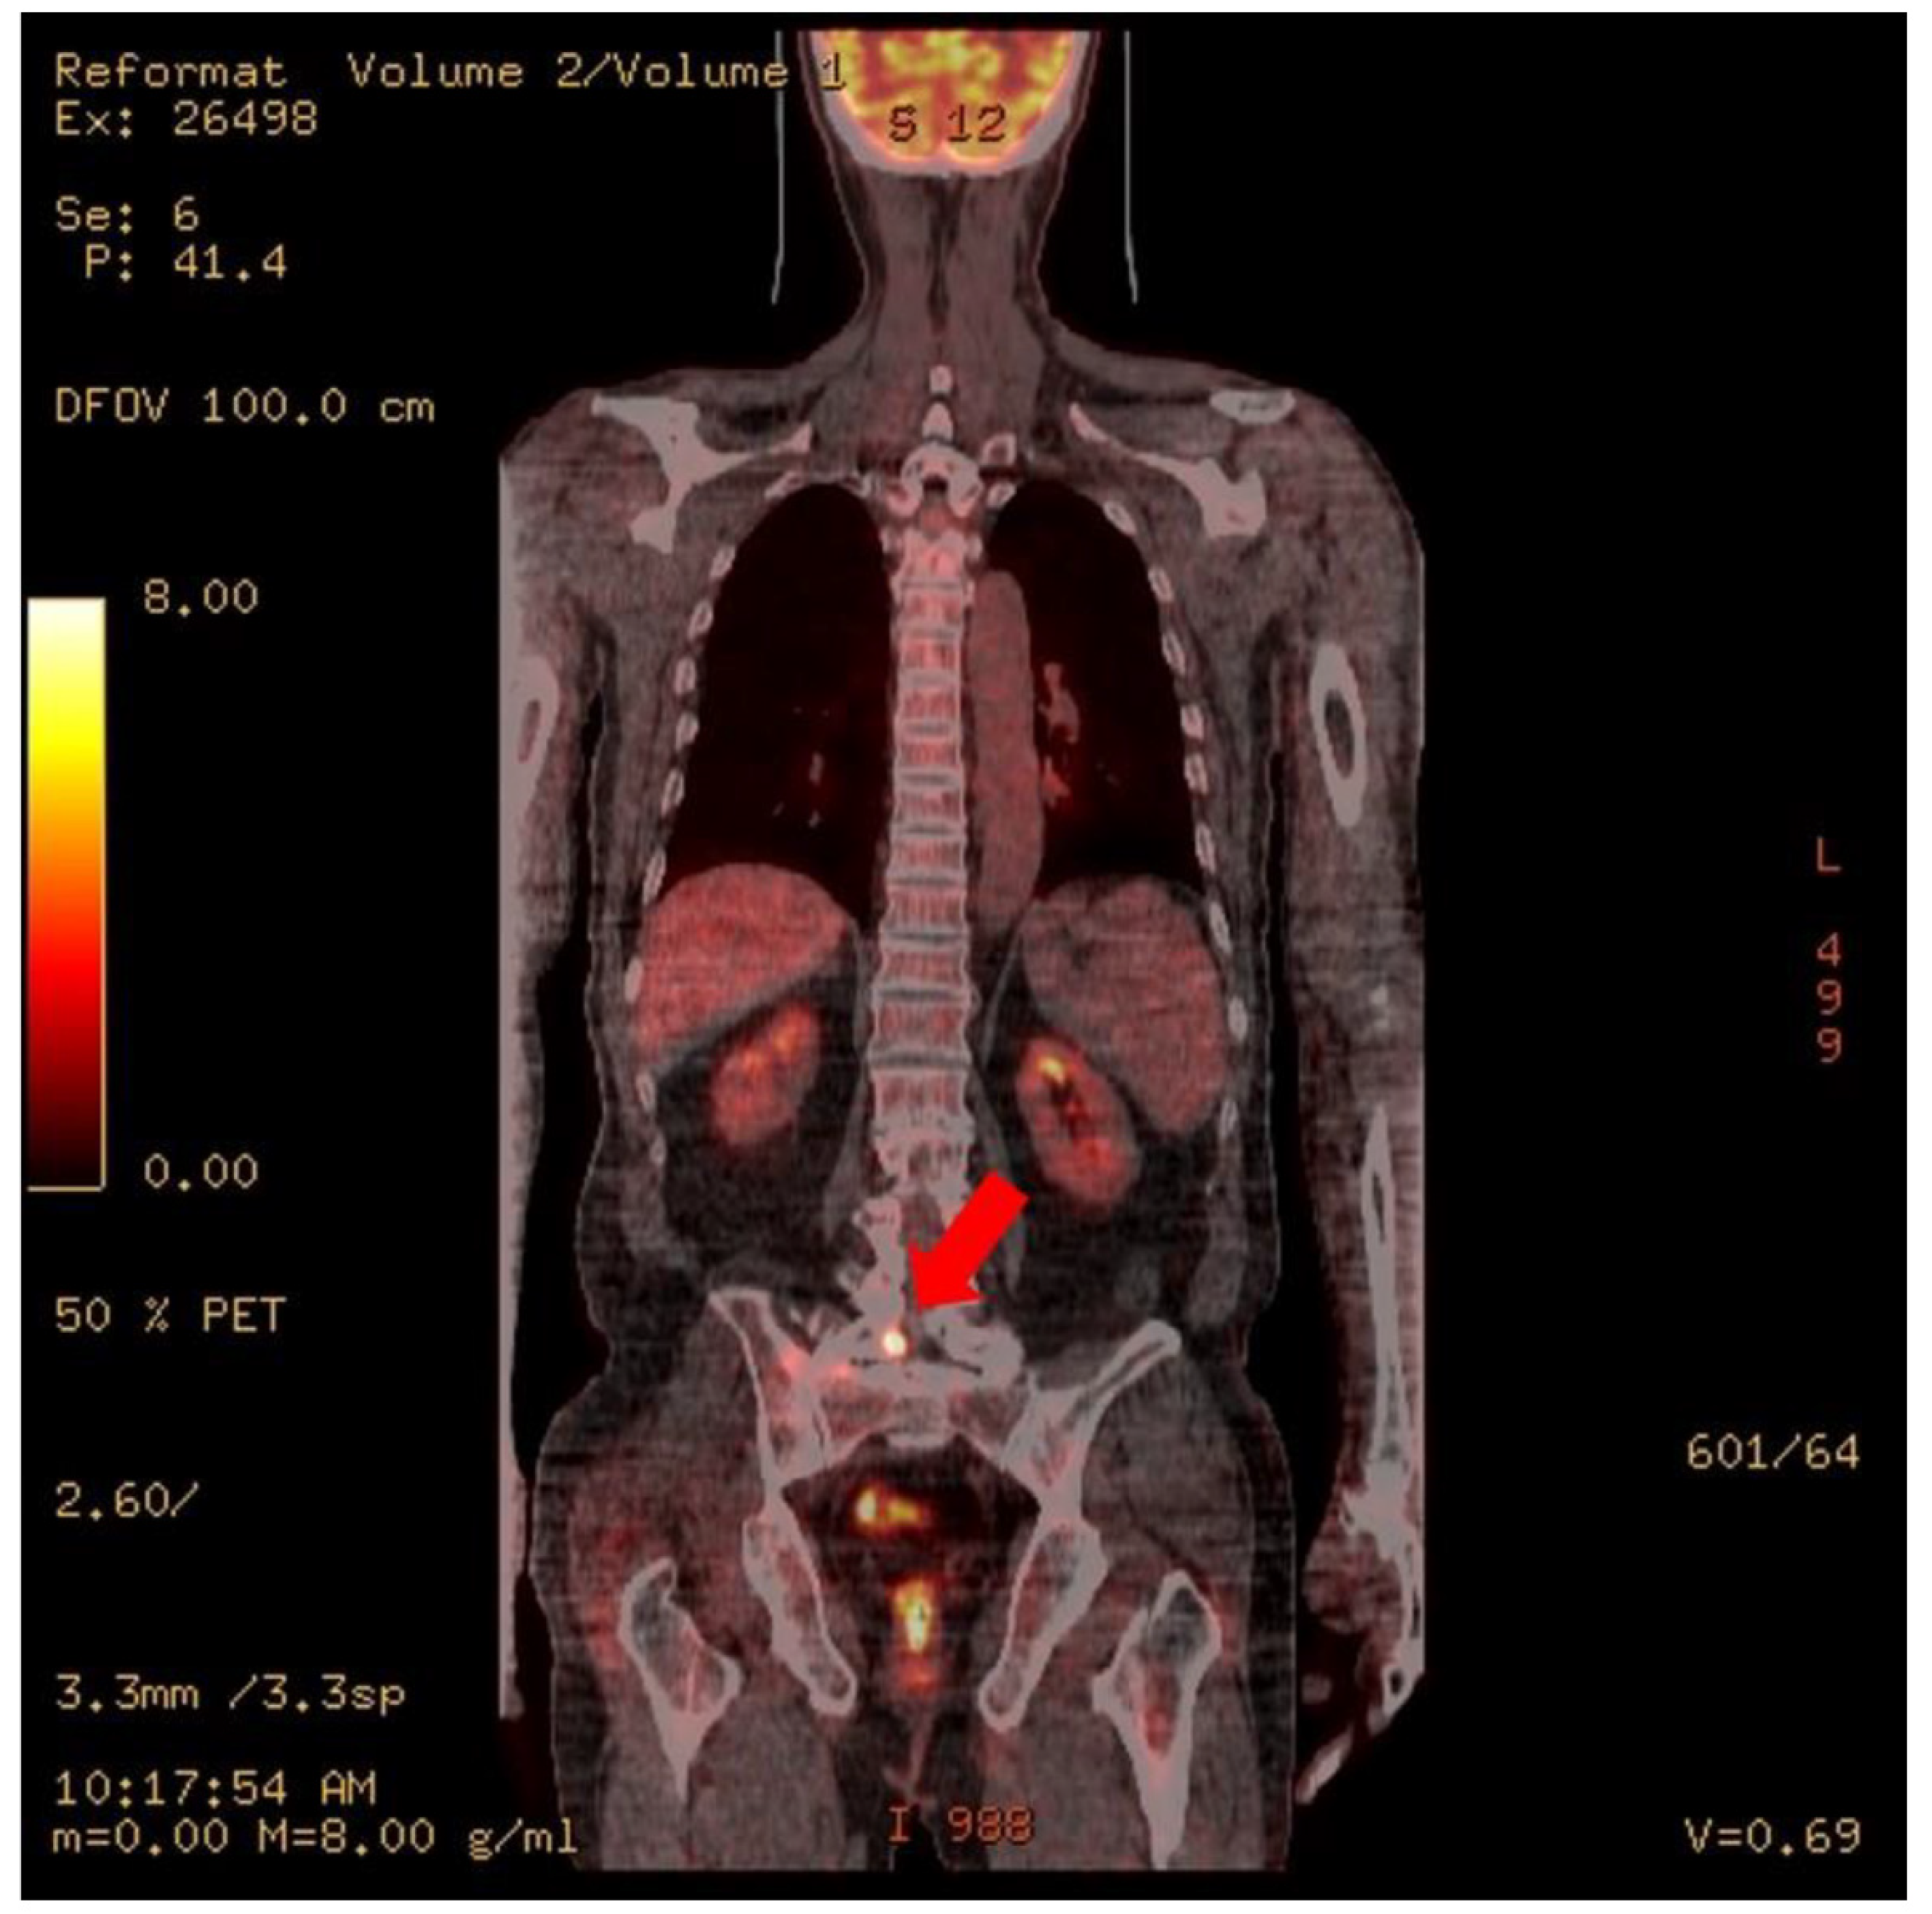

At the time of admission to the Hematology Oncology Department, an MRI of the lumbar spine showed suspicious findings of multifocal bone metastasis in the thoracic-lumbar spine, including T11-L5 and bilateral sacrum, iliac bones and epidural metastasis at L4/5, L5/S1 and the sacrum (Figure 1). PET-CT was also performed after the third R-CHOP at the time of admission to the Department of Hematology and Oncology, and showed residual hypermetabolic lesions in L5, the sacrum, and the right presacral area (Figure 2). Electrodiagnostic examination was performed five months after the onset (Table 1).

Figure 2. PET CT. Focal increased uptake is noted at right L5, the sacrum, and the presacral area (arrows).